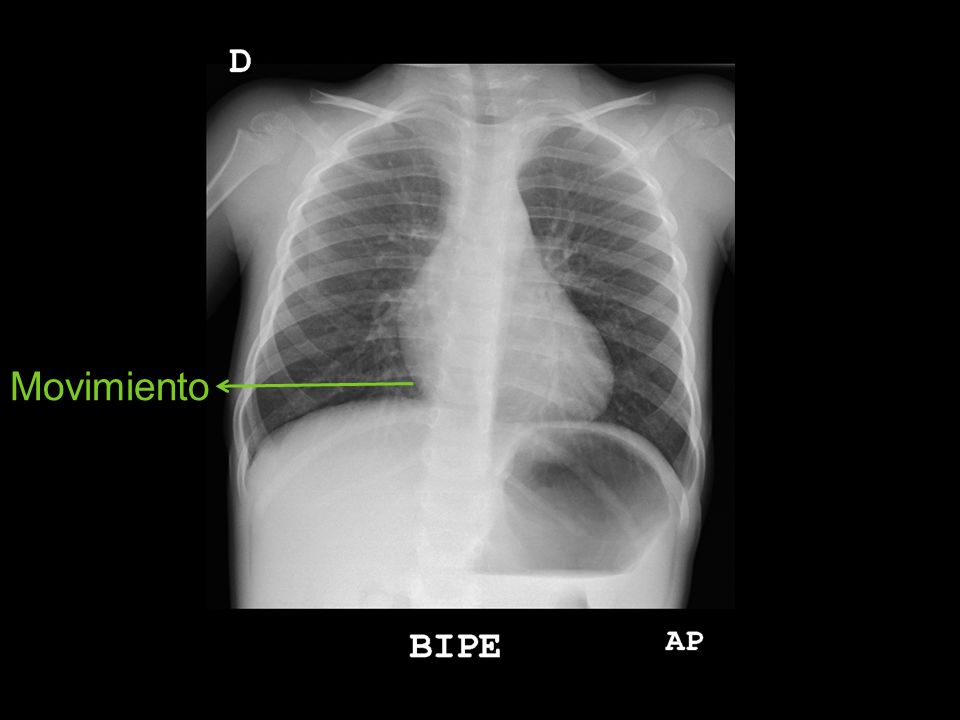

• Movimiento: pérdida de la definición del contorno mediastínico y de los vasos pulmonares.